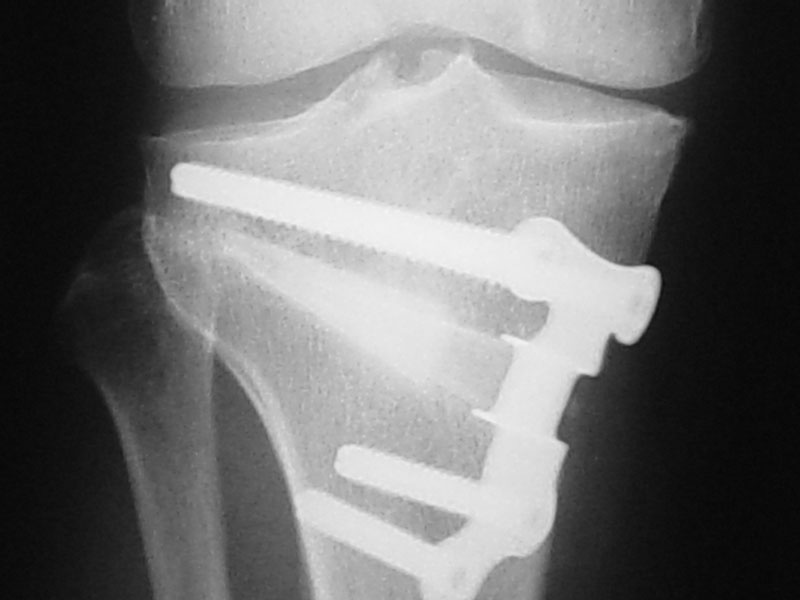

Realignment procedures are called osteotomies. These involve cutting the tibia or femur bone and changing the overall alignment of the leg to make it more “knock-kneed” or sometimes more “bow-legged”. The aim is to take weight away from the part of the knee that is affected by osteoarthritis. Such procedures can only be used in certain patterns of osteoarthritis and are better suited to people under the age of 55. They can however provide good long-term relief and put off the need for joint replacement, whilst at the same time allowing an individual to remain quite active.

Osteotomies can be performed above or below the knee joint. For medial compartment osteoarthritis, osteotomies are most commonly performed by operating on the upper tibia. If the osteoarthritis is in the lateral compartment, the osteotomy is usually performed in the lower femur.

The osteotomy procedure itself involves cutting the bone virtually completely. There are then two ways of realigning the bone. One is to take out a wedge of bone and the other is to make a cut and open up a wedge and fill it with either bone or a bone substitute. If a bone is used, it can either be allograft bone which is taken from a cadaver, or autograft bone which is taken from the patient, usually from the hip region. Some kind of metallic fixation device, usually a plate with screws, is then used to stabilise the osteotomy while it heals. In general, there has been a trend moving away from so-called closing wedge osteotomies, where a wedge of bone is taken out, towards opening wedge osteotomies, where a cut is made and the wedge is opened. There are potential advantages and disadvantages of each technique and a decision regarding the most appropriate method will be based on your individual situation.

In addition, surgery around the front of the knee is often associated with difficulty kneeling. This is more of a problem with tibial osteotomies than with femoral osteotomies. The metallic plate that is used to fix the osteotomy can be prominent, particularly in thin people. If this is the case the metallic hardware can be removed after about 12 months following surgery. This is usually done as a day or overnight case. Sometimes the metallic hardware is removed routinely after 12 months, although this is at the discretion of your surgeon. However, if a knee replacement is planned the hardware will need to be removed prior to this procedure.